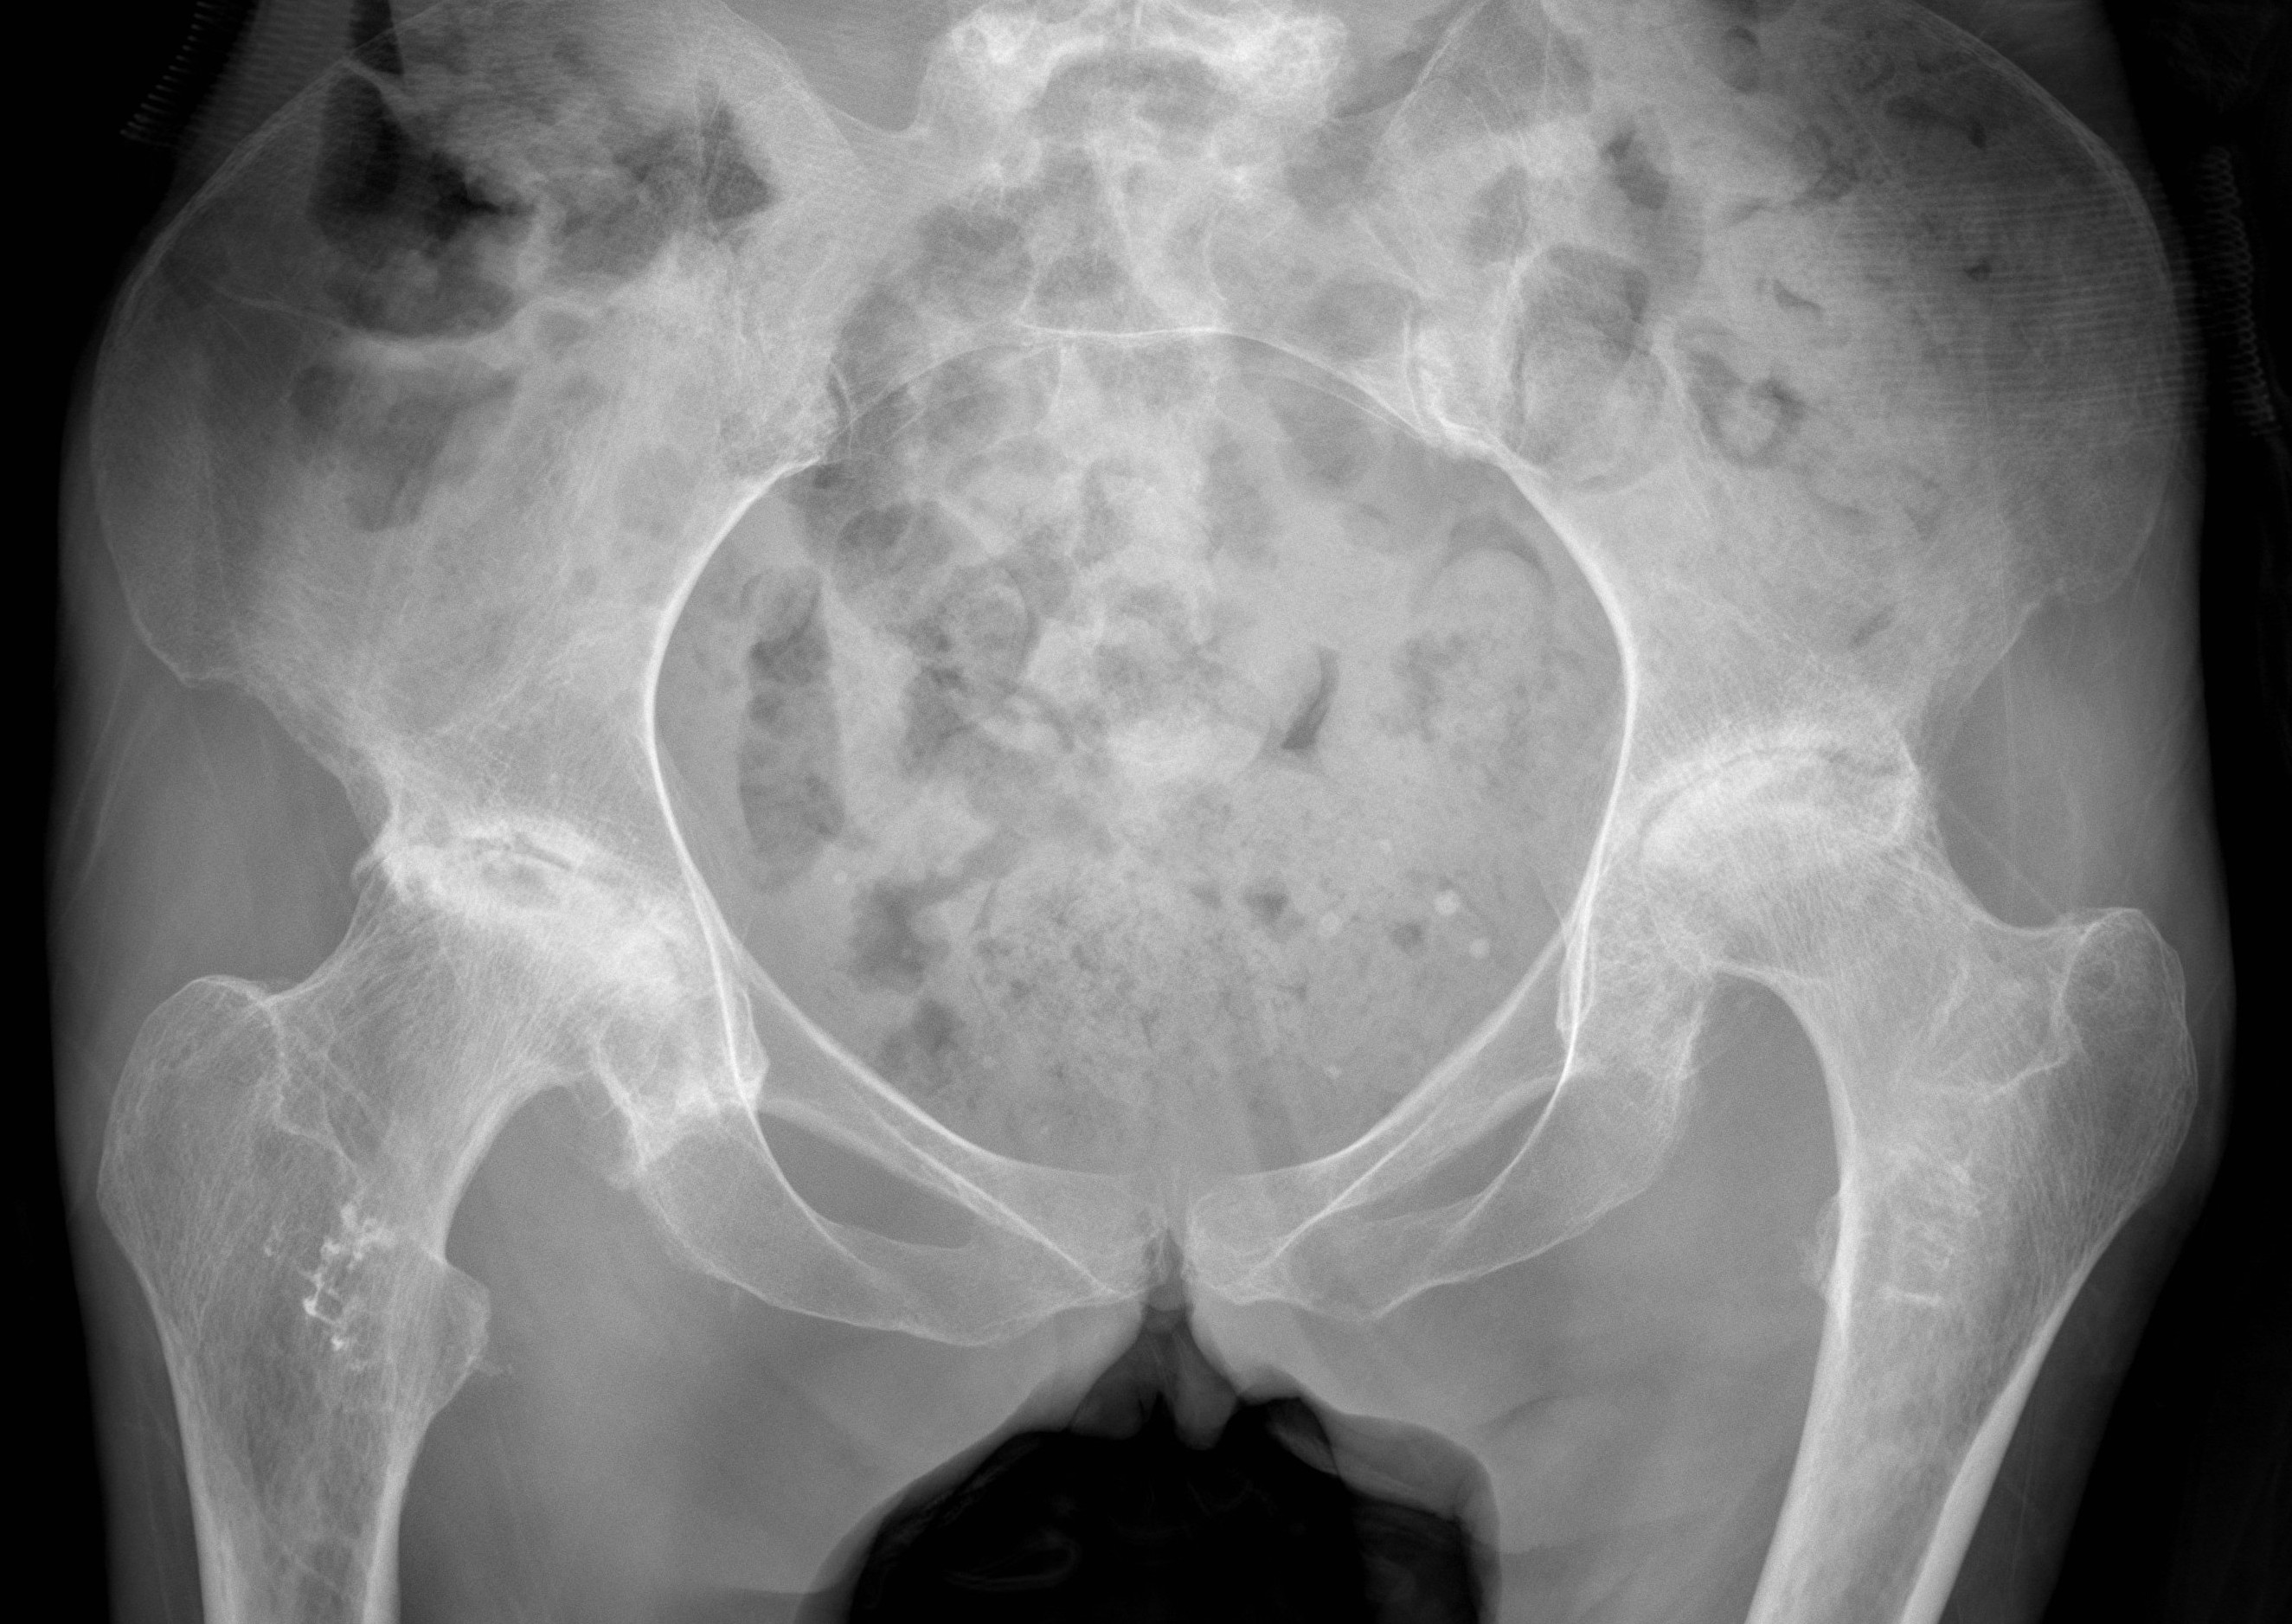

Xray

Stage II: sclerosis with cystic areas resorption, no collapse

Stage III: collapse / flattening femoral head with preserved joint space

Stage IV: Collapse with osteoarthritis